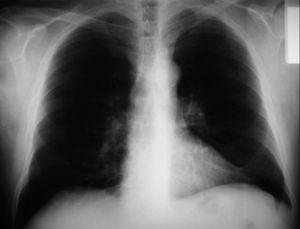

Paciente de 66 años, fumador de 40 paquetes/año, con antecedentes de arteriopatía aterosclerótica de los sectores femoropoplíteos y carotídeos bilaterales, tratada médicamente, que ingresó para estudio de pérdida de la visión de los colores, tras faquectomía bilateral sin complicaciones. Su oftalmólogo indicó que se trataba de un síndrome paraneoplásico y recomendó una evaluación para descartar un posible tumor. La exploración física mostró un Karnofsky del 80%, sin evidencia clínica de enfermedad. La colonoscopia y la gastroscopia descartaron la presencia de enfermedad. La radiografía posteroanterior de tórax reveló sólo un hilio izquierdo ensanchado (fig. 1). La tomografía computarizada torácica mostró una lesión de aspecto tumoral de 2,5 cm, localizada en el segmento posterior del lóbulo inferior izquierdo (fig. 2), que no captó contraste, con discretas atelectasias subsegmentarias en esa zona. También reveló cambios enfisematosos en los lóbulos superiores. En el mediastino no se identificaron adenopatías de tamaño patológico. El hígado y las suprarrenales no mostraron lesiones. La broncoscopia evidenció una lesión endobronquial en el segmento posterior del lóbulo inferior izquierdo, que estenosaba totalmente la luz bronquial. La citología del broncoaspirado fue positiva para carcinoma, y la biopsia resultó positiva para carcinoma escamoso no queratinizante. El estudio funcional respiratorio estuvo dentro del rango de la normalidad, con un índice volumen espiratorio forzado en el primer segundo/capacidad vital forzada (2,58/3,54) sobre el 80% del teórico. La gasometría arterial fue normal. La gammagrafía ósea no reveló imágenes compatibles con metástasis.

Fig. 1. Placa posteroanterior preoperatoria, sin evidencia de tumor bronquial.